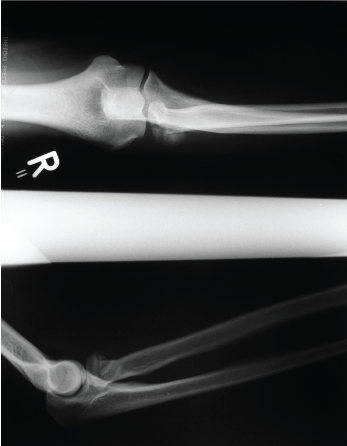

Case 1: Images 1a-d

Images of a 38 year old patient after a fall while inline skating. It was a Mason II radial head fracture with a fracture of the capitullum. Follow-up after 39 months; extension/flexion in elbow 0-5-140; pronation/supination 90-0-90. The patient had a Morrey score of 93 points and good results according to R & R.